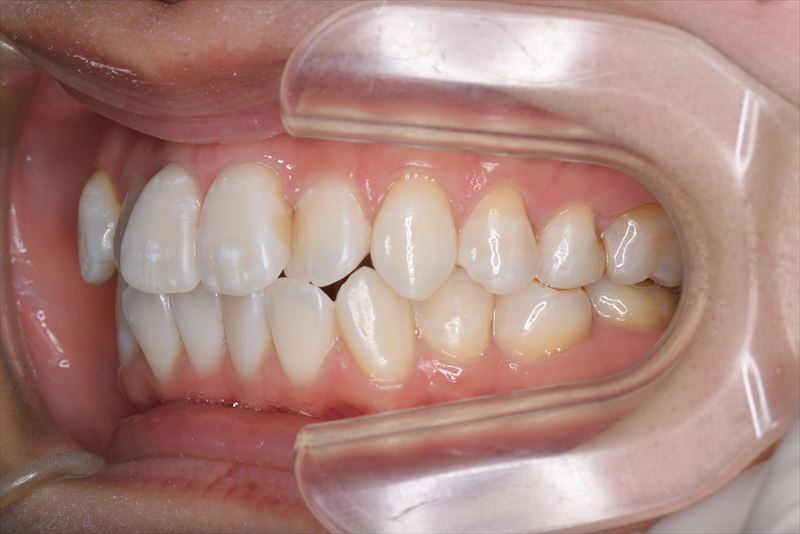

治療後

- 両側2番クロスバイト、叢生、上顎左側6番根尖病巣

- 上顎左側6番は失活歯で根尖病巣を認めたため抜歯し、上顎左側8番を代わりに使用することとしました。アンカースクリューを使用することにより、健康な歯を抜歯せず臼歯の遠心移動で叢生の改善できました。治療期間が短かく良好な咬合を獲得できました。